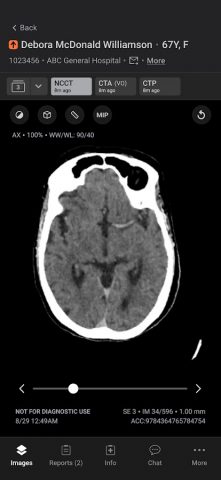

Мобильное приложение Aidoc оптимизирует коммуникацию, ускоряя принятие решений в критических ситуациях и повышая качество медицинской помощи. Приложение обеспечивает приоритезацию и оповещение на основе ИИ о широком спектре острых патологий, включая окклюзии крупных сосудов и легочную эмболию, — все это через защищенное мобильное приложение, соответствующее требованиям HIPAA.

Автоматически работающий ИИ Aidoc автоматически получает и анализирует все соответствующие исследования для выявления подозрительных результатов. После того, как исследование отмечено, Aidoc выделяет подозрительные результаты непосредственно в рабочем процессе медицинской визуализации. При остром состоянии изображения и соответствующие данные электронной медицинской карты (включая тенденции) передаются в мобильное приложение для своевременного вмешательства медицинской бригады. Врачи могут устанавливать свои предпочтения в мобильном приложении, включая индикацию вызова, указание места проведения исследования и конкретные рабочие процессы. Aidoc помогает сократить время от сканирования до постановки диагноза, повышая эффективность, сокращая время до начала лечения и улучшая качество медицинской помощи.